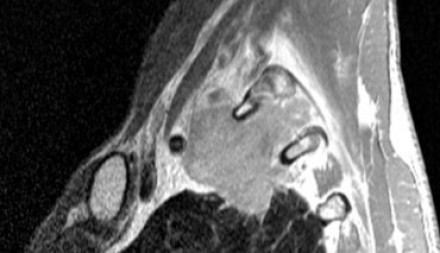

Выполнение МРТ приоритетнее в связи с лучшим мягкотканным контрастом в сравнении с КТ. |

На Т1-изображениях представлен пациент с раком Панкоста Т3-стадии в связи с тем, что поражены корешки только Th1, Th2